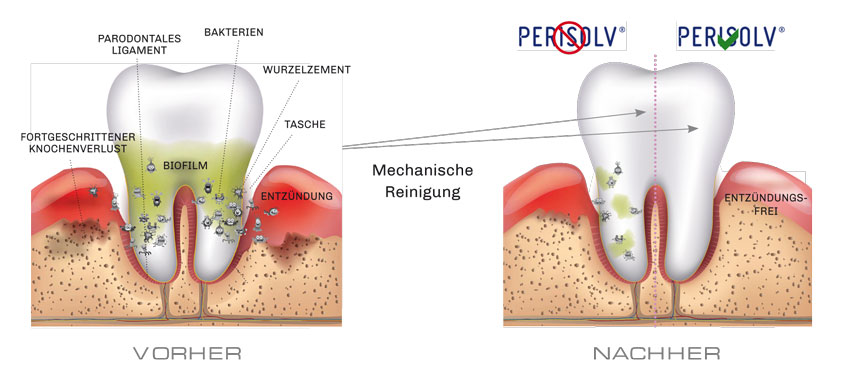

MODE OF ACTION

Mechanische Reinigung mit und ohne PERISOLV®

* Fördert bei der mechanischen Reinigung die Entfernung der Bakterien.